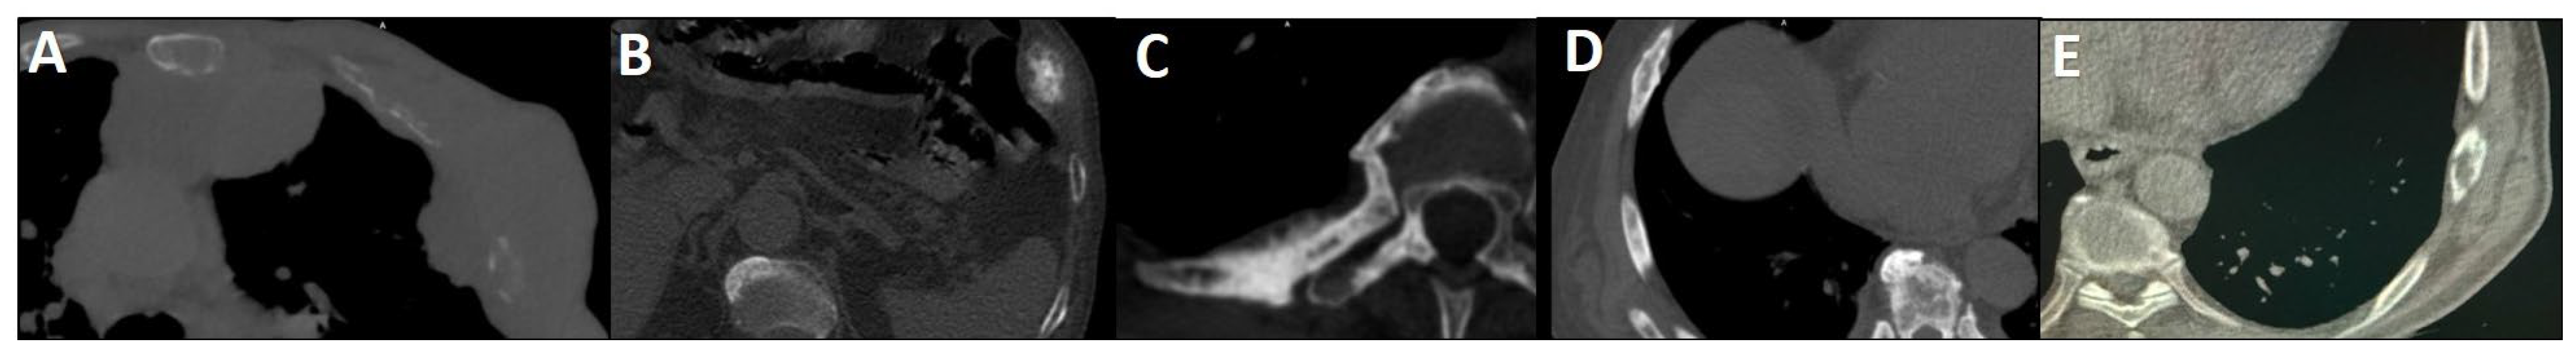

Figure 5.

PSMA scan ruling out the possibility of metastatic prostate cancer. A 73-year-old man was referred for diagnosis/staging, due to mildly elevated serum PSA levels, and a few lytic–sclerotic bone lesions incidentally found in the recent abdominopelvic CT scan. Whole-body 99mTc-PSMA (A,B) and SPECT/CT (C) showed faint PSMA uptake in the prostate gland (PRIMARY score 1) with multiple non-PSMA-avid (white arrows) lytic–sclerotic changes in the L4 vertebra (D), sacrum (E), left iliac (F) and left 6th rib (G). No nodal or visceral involvement was evident. These bone lesions were finally concluded as unrelated pathology to prostate cancer, yet the rare possibility of non-PSMA-avid tumor could not be entirely ruled out.